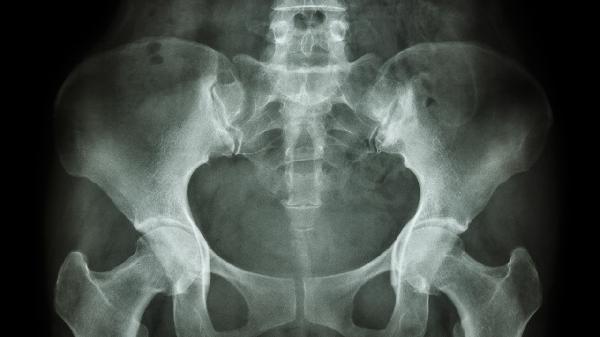

耻骨突出可能由生理性因素、外伤、骨盆畸形、妊娠相关改变或肿瘤性疾病引起。

耻骨区域骨软骨瘤或转移性肿瘤可能导致局部骨质膨隆。这类突起通常进展较快,可能伴有夜间痛和体重下降,影像学检查可见特征性骨质破坏或软组织肿块。

日常应注意避免长时间单侧负重,选择软底鞋减轻骨盆冲击力。建议每周进行3-4次骨盆稳定训练,如桥式运动、侧卧抬腿等,每次20-30分钟。饮食需保证每日1000-1200mg钙摄入,多食用乳制品、深绿色蔬菜。出现进行性加重的疼痛或排尿异常时,应及时进行骨盆X光或MRI检查。